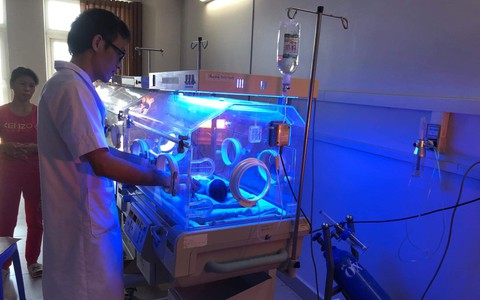

TTO - Một tài xế taxi trẻ tuổi, nhanh trí và có trách nhiệm ở Thanh Hóa đã rất nỗ lực khi trong một thời gian ngắn đã đưa mẹ con một sản phụ đến Bệnh viện Đa khoa Hợp Lực cấp cứu kịp thời. Câu chuyện đẹp này đang lan tỏa trên mạng xã hội.